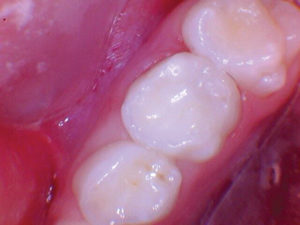

Figura 7. Después del ataque

con ácido y el uso del agente de unión Scotchbond Universal (3M), los dos

molares primarios superiores se restauraron con Activa Bioactive Restorative

A2. |